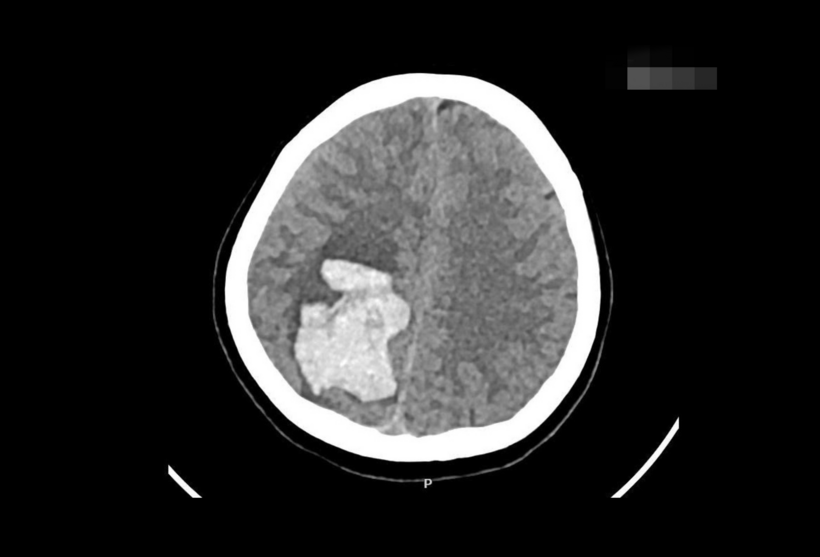

Ngay lập tức, bệnh viện kích hoạt y lệnh khẩn “Code Stroke” (quy trình cấp cứu đột quỵ não, được thiết lập để tối ưu hóa thời gian và nâng cao hiệu quả điều trị cho bệnh nhân - PV), mở lối ưu tiên cấp cứu. Khảo sát hình ảnh học ghi nhận chị Quyên có ổ xuất huyết nội sọ lớn ở bán cầu não phải, kích thước khoảng 5x4x6 cm trong nhu mô não đính chẩm phải. Khối máu tụ gây chèn ép mạnh và đẩy lệch đường giữa não - dấu hiệu tình trạng tăng áp lực nội sọ nguy kịch. Đây là tình huống tối cấp. Nếu chậm trễ, nguy cơ đe dọa tính mạng cả mẹ và thai nhi rất cao.

Hình ảnh xuất huyết não của thai phụ mang thai ở tuần 19. Ảnh: BSCC